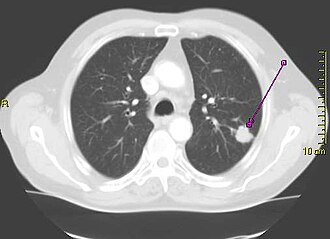

Najčešći uzrok karcinoma pluća je dugotrajno pušenje duhana,[2] koje uzrokuje 80–90% slučajeva karcinoma pluća.[1] U nepušača se razvija 10–15% slučajeva karcinoma pluća,[3] a ti se slučajevi pripisuju kombinaciji genskih čimbenika,[4] izlaganju plinu radonu,[4] azbestu,[5] te zagađenju zraka[4] u koje spada i pasivno pušenje.[6][7] Karcinom pluća se može otkriti rendgenom pluća i kompjuteriziranom tomografijom (CT). Dijagnoza se potvrđuje biopsijom[8] koja se obično izvodi bronhoskopijom ili uz pomoć CT-a. Liječenje i dugoročni ishod ovise o vrsti karcinoma kliničkom stadiju bolesti (proširenosti) i procjeni sveukupnog zdravstvenog stanja bolesnika.

Jedna od prvih pretraga u osobe sa simptomima koji bi mogli ukazivati na karcinom pluća je rentgen prsišta. Njime se može otkriti jasna tumorska masa, proširenje medijastiuma (koje ukazuje na tumorsko zahvaćanje limfnih čvorova u tom području), atelektazu (kolaps pluća), konsolidaciju (pneumoniju) ili pleuralni izljev.[2] CT se tipično koristi za dobivanje podrobnijih podataka o vrsti i proširenosti bolesti. Bronhoskopija ili biopsija pod kontrolom CT-a se često koristi za uzimanje uzorka tkiva tumora u svrhu patohistološke pretrage.[10]

Na rentgenskoj slici pluća karcinom pluća se često očituje kao pojedinačni čvor u plućima. Međutim, u tom je slučaju diferencijalna dijagnoza vrlo široka. Mnoge druge bolesti mogu se očitovati na isti način, uključujući tuberkulozu, gljivične infekcije, metastazu raka iz nekog drugog primarnog sijela i organizirajuću pneumoniju. Manje učestali uzroci pojedinačnog čvora u plućima su hamartomi, bronhogene ciste, adenomi, arteriovenska malformacija, plućna sekvestracija, reumatoidni čvorovi, Wegenerova granulomatoza ili limfom.[42] Rak pluća može biti i slučajni nalaz, na retgenskoj slici ili CT-u pluća učinjenima iz nekog drugog razloga.[43] Konačna dijagnoza karcinoma pluća postavlja se na osnovi histološke pretrage tkiva koje je sumnjivo na osnovi kliničkih i rentgenskih osobina.[1]